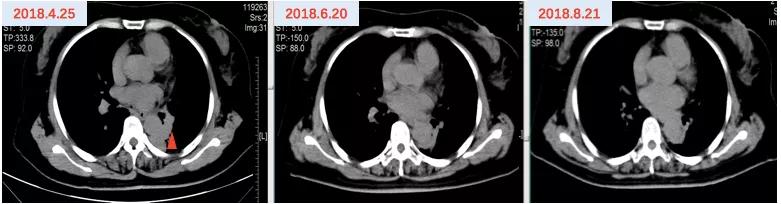

2018年4月20日开始口服“吉非替尼250mg qd”靶向治疗至2019年2月27日,疗效评价SD,PFS约10月。(图4、5)

图4 吉非替尼治疗前CTA

图5 吉非替尼治疗期间CT影像